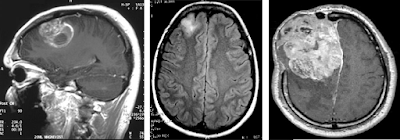

Ironicamente, apesar da maioria das premissas básicas da frenologia terem sido consideradas pseudociência, as leituras dos comportamentos e a sua relação com o crânio não foram. O princípio de que as funções específicas cerebrais estão localizadas em topografias determinadas é agora conhecimento comum demonstradas por técnicas modernas de imagem, como a ressonância magnética funcional (FMRI). Esta doutrina que possibilita a visualização precisa de uma determinada função quando ela está sendo realizada é chamada de localizacionismo cerebral.